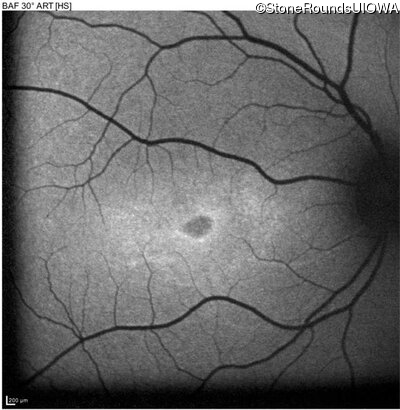

Age at visit: 17 years

OD OS

This 17 year old female first noted problems with her visual acuity around age 13 when she had trouble seeing the projector from the back of the classroom.